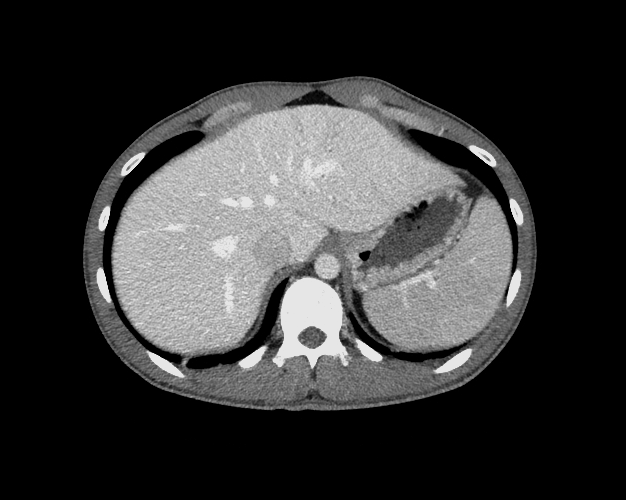

Body

Covers abdominal CT anatomy.